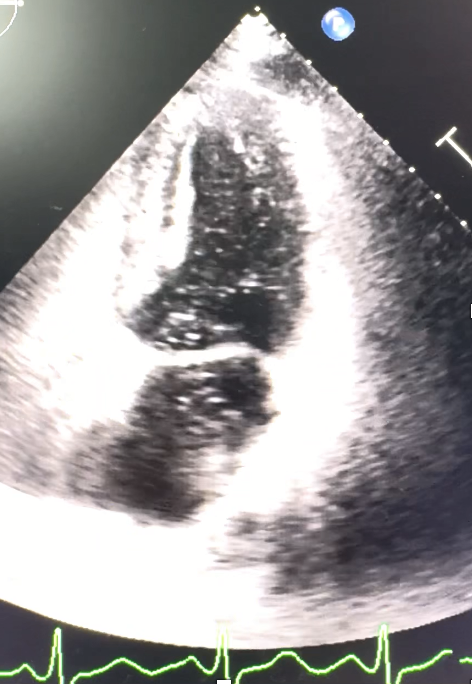

We access right radial artery using 5/6 F sheath, IL 3.5 catheter.Angiogram showed total occlusion at distal segment of OM1 branch and distal LAD. Then we injected RCA which no significant stenosis. We thought the culprit lesion was distal OM branch then we planned to engage Left coronary again. Just a seconds after we prepared to engaged left system again, patient suddenly developed hypotension and then cardiac arrest. Simultaneous CPR and left coronary system injection were performed. At this time, the left system showed the total occlusion of left main coronary artery!! With TIMI 0 flow. We advanced the Runthrough wire to cross the left main into LAD. 2.0 x 15 mm balloon was predilated at distal left main lesion. After predilate the balloon, slow flow was demonstrated to LAD but there was No flow to Lcx.Wiring to Lcx with Sion blue wire was done. Then we deployed 3.0 x 21 mm DES to Left main-LAD.Angiogram after stent deployment showed TIMI II flow to LAD but Lcx still TIMI 0 flow. We performed POT in the Left main stent with 4.0 x 8 mm NC balloon -> after POT , flow to Lcx was restored but there was new total occlusion at distal Lcx.IABP was inserted. IVUS confirm wire was in false lumen. we placed 2.5 x 18mm DES to distal Lcx after rewiring.We also search for etiology of MI in the young. Echo showed high risk PFO -> successful PFO device closure.Final diagnosis was coronary emboli cause STEMI + guide-induce left main dissection and wire-induced Lcx dissection.

We also search for the etiology of MI the young patient with non-smoking. All hypercoagulable state were negative. Echocardiogram showed good LVEF but the agitated saline bubble test was positive with > 30 microbubbles during Valsalva¡¯s maneuver. High risk PFO was diagnosed. An 25/18 mm PFO device closure was done. So, the final diagnosis is coronary emboli causing acute inferior wall STEMI with the guiding-induced left main dissection during coronary angiogram.